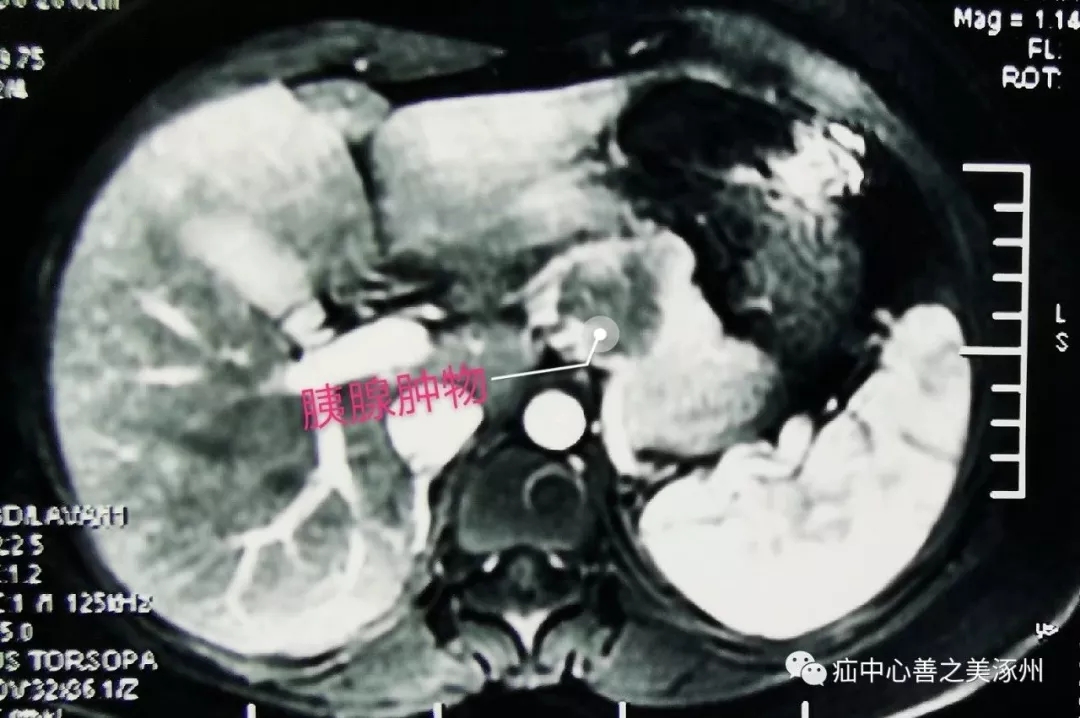

近日,我们普外二科成功为一名胰腺肿物患者行“全腹腔镜下保留脾脏的胰体尾切除术”。患者手术顺利。该项手术加快了我院在腹腔镜胰腺手术方面的进步。患者为青年女性,因体检发现胰腺肿物入院。增强CT提示胰体部一囊实性占位性病灶,病灶紧邻脾动脉和脾静脉,术前保定252医院CT诊断考虑胰腺假乳头状瘤可能性较大。

在麻醉科、手术室的配合下,在白金宝主任医师指导下,邓新生主任带领“宝之队'”团队通过腹腔镜探查发现肿瘤位于胰腺体尾部,其直径约3cm,囊实性,后方紧邻脾动、静脉,并且脾血管受压。腹腔镜下进行了精细的分离、在动静脉表面分离组织,就如在刀尖上跳舞。充分游离,直线切割闭合器离断胰腺,逐支结扎脾动静脉分支血管,保留脾脏,完整切除胰体尾,手术出血不足30毫升。以往这类手术都是采用传统开腹手术,创伤大,切口长,恢复慢。我院普外科近些年陆续开展了各类腔镜手术,为全腹腔镜下胰腺胰腺手术奠定了技术基础,它不仅成功地保留了脾动、静脉,且术中出血少。此次手术的完成,填补了我院该领域的空白。标志着我院腹腔镜微创高难度、高风险手术技术取得新的突破,再上新的台阶。